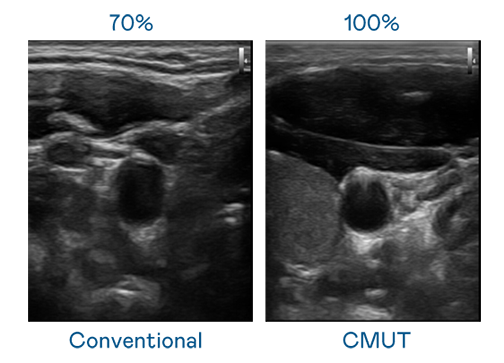

CMUT 技术是一种用电容式微机电元件来产生超音波讯号的技术。与传统 PZT 压电式技术相比,CMUT 频宽增加 30%,更宽频的超音波讯号让影像解析度大幅提升,是实现高影像品质医疗超音波扫描、促进精准医疗发展的关键技术。

大频宽带来超清晰影像

超音波影像的解析度高低,首先取决于探头能发出的讯号频宽。金年会金字招牌信誉至上入口 CMUT 可提供高清晰的超音波讯号,提供高频宽、高灵敏度、影像纹理细节更高的超音波影像,协助医护人员缩短影像判读时间及利用精准的医疗影像进行诊断。